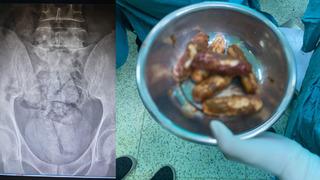

Hepsini bağırsağında saklamış! Artvin'de İranlı şüpheli gözaltına alındı

Artvin'de bağırsağından 350 gram metamfetamin çıkan İran uyruklu F.R. (43) gözaltına alındı.